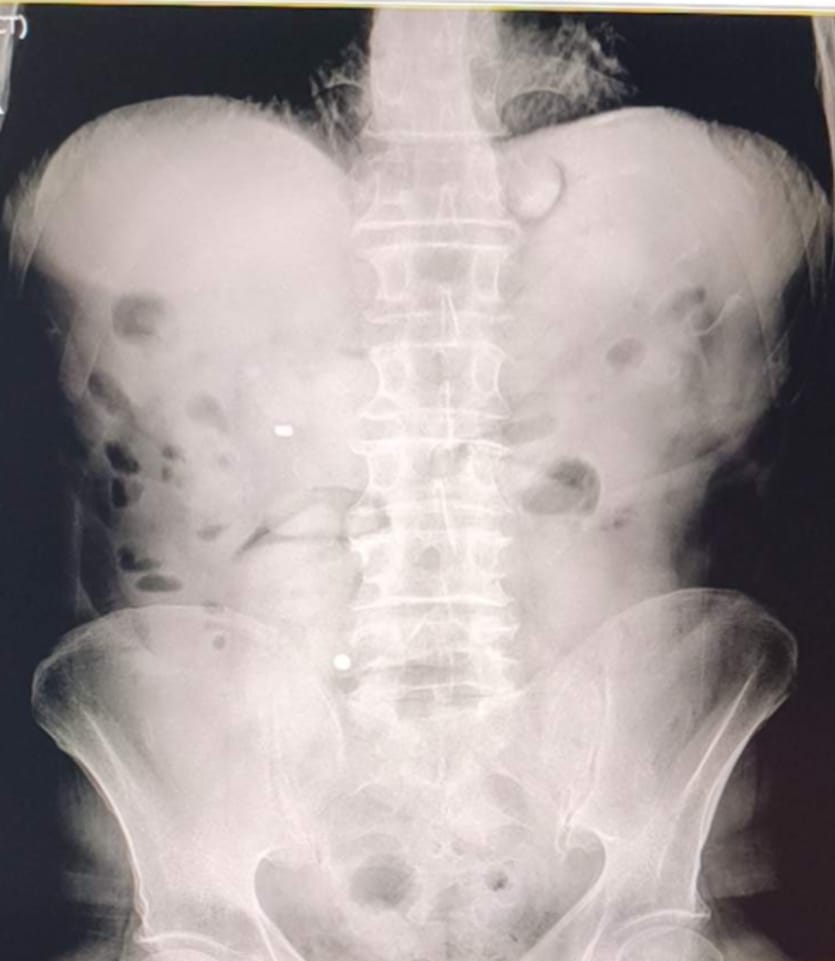

Uşak İl Emniyet Müdürlüğünce “Uyuşturucu veya Uyarıcı Madde İmal ve Ticareti” suçu kapsamında yürütülen çalışmalar ve takipler neticesinde il merkezimizde yakalanan İran uyruklu 2 şüpheli şahsın hastanede yaptırılan kontrolleri ve çekilen röntgen filmleri neticesinde mide ve bağırsaklarında çok sayıda uyuşturucu madde içeren kapsül bulunduğu tespit edildi, hastanede kontrollü bir şekilde gözetim altında tutulan şüphelilerden tıbbi müdahaleler neticesinde toplam;

93 parça halinde, 1 kilo 70 gram Metamfetamin ele geçirildi..